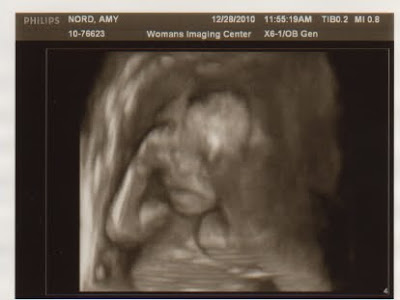

Ultrasound Pics at 18 weeks in the words of baby....

Dec- What a busy month getting ready for Christmas. We had so much to celebrate this month. On the 28th we found out we were having a little boy and on the 30th we celebrated 15 wonderful years of marriage! What an amazing month! We also found out I have placenta previa but that our little boy is perfectly healthy, it just means mommy has to take it very easy for a while.